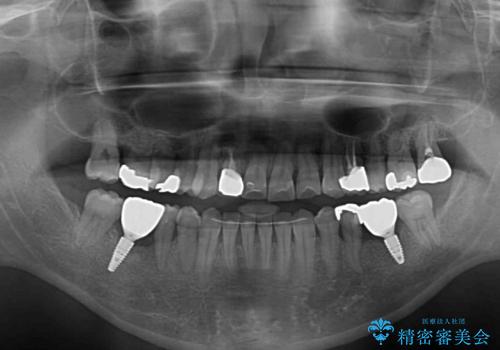

- 奥歯の痛みと前歯のデコボコを気にして来院された患者様です。

左右下顎の大臼歯は、ともに歯根が破折しており、抜歯が必要な状態でした。

放置したことで炎症による骨吸収が顕著であるため、骨造成を併用してインプラント埋入を行うこととしました。

咬み合わせは受け口傾向であり、上顎前歯の叢生が顕著であったことから、第1小臼歯抜歯による矯正治療も検討しましたが、下顎大臼歯を左右ともに抜歯するため、非抜歯による矯正治療を行うこととしました。